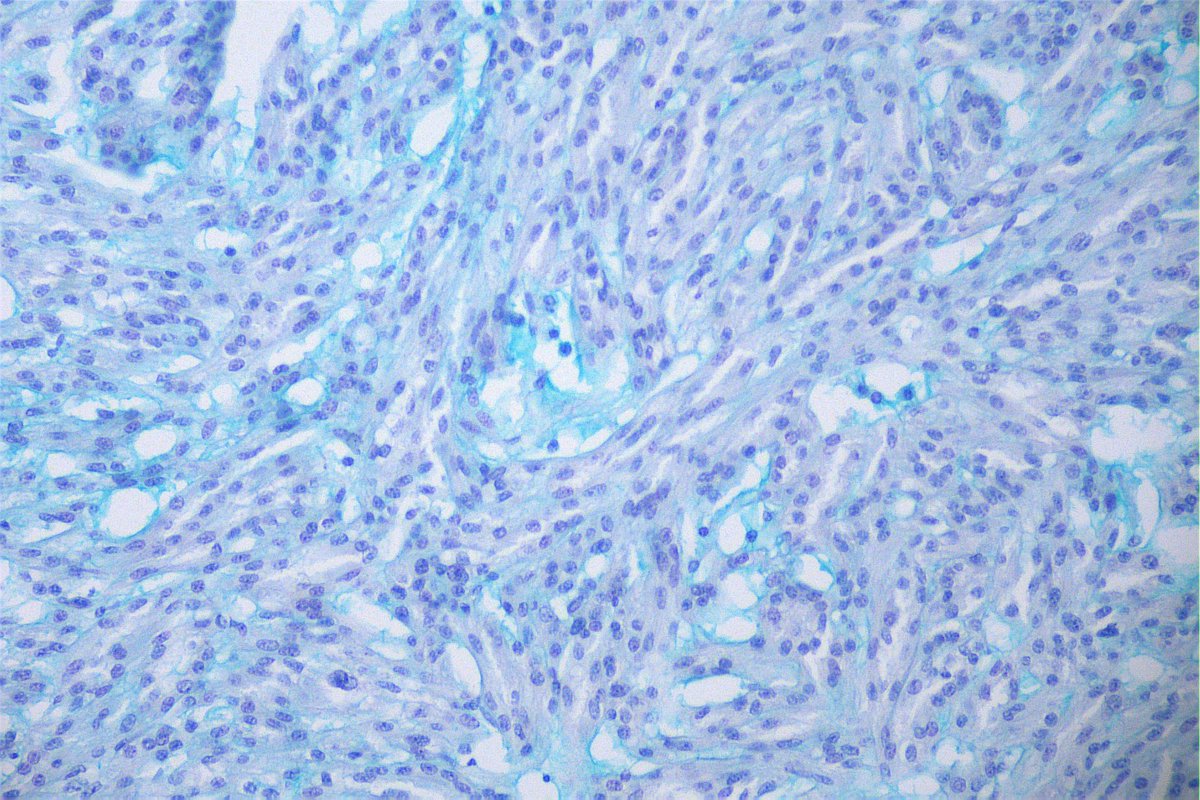

Case of the day. M, 30 years old, with weight loss, pulmonary consolidation area, mediastinal lymph node enlargement, and endobronchial polypoid lesions. Bronchial biopsy performed. #pulmpath #pathology